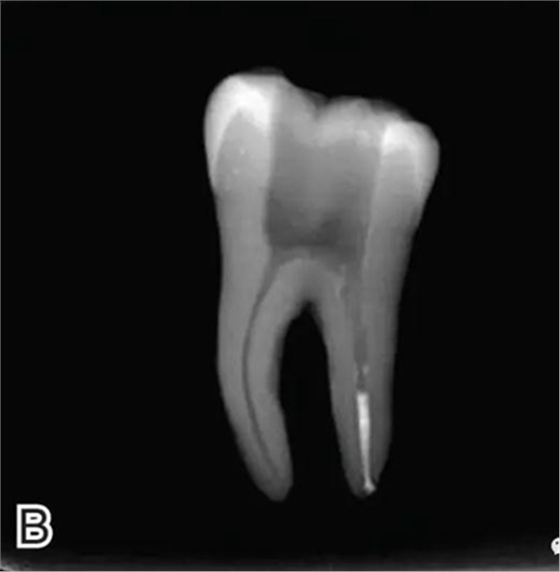

在完成根尖段的充填后,使用熱塑牙膠注射儀對根管中上段進(jìn)行分層充填,一般分2~3次完成充填,每次充填均使用相應(yīng)直徑大小的垂直加壓器進(jìn)行加壓。拍片確認(rèn)充填效果(圖8)。

圖8 熱牙膠根中上段的充填,A、B.注射儀注射中段熱牙膠

C、D.垂直加壓器加壓 E、F.注射儀繼續(xù)注射上段熱牙膠

G、H.垂直加壓器加壓 I、J.完成根中上段的充填